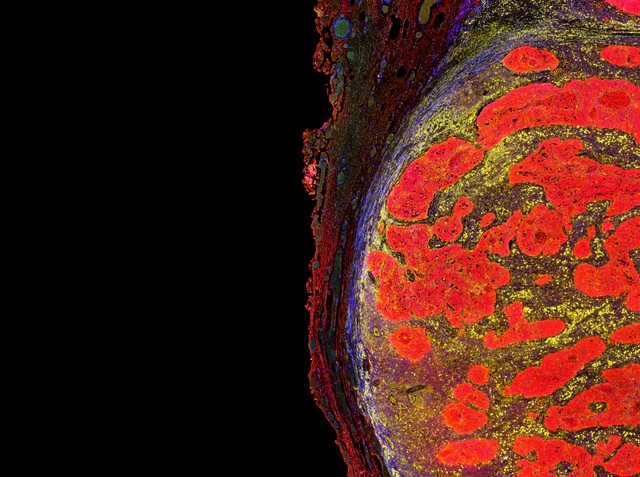

Daganatos betegségek

Speciális tapaszt fejlesztettek ki a tumornövekedés nyomon követéséhez

Kínai kutatók fejlesztettek ki egy eszközt, amely alkalmas a bőr alatti tumorok méretének monitorozására.